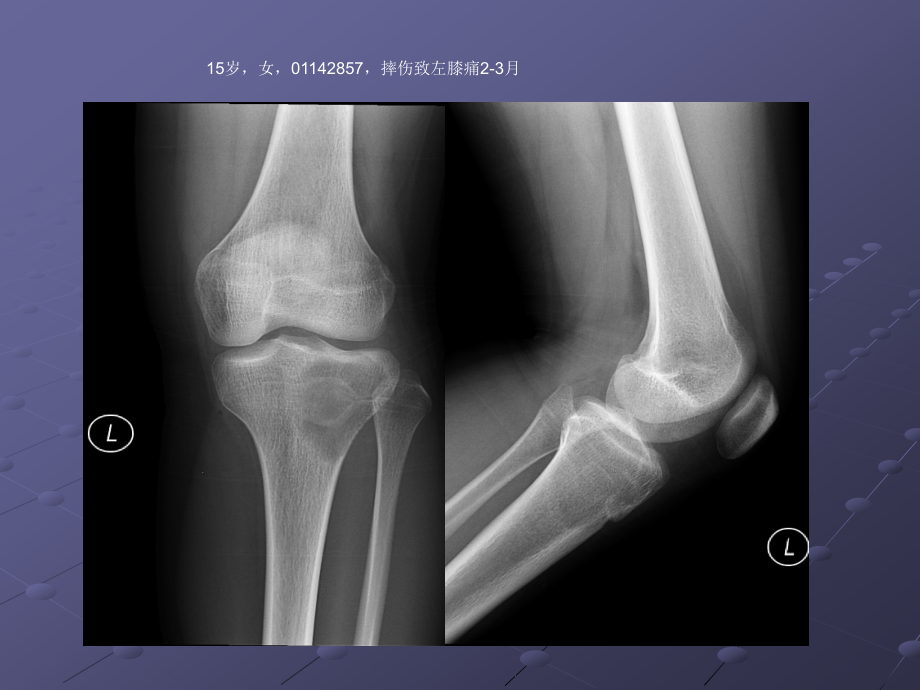

,*,单击此处编辑母版文本样式,第二级,第三级,第四级,第五级,单击此处编辑母版标题样式,15岁,女,01142857,摔伤致左膝痛2-3月,胫骨软骨母,12岁,男,,软骨母细胞瘤的影像诊断,福建医科大学附属第一医院影像科-李玉萍,2015.07.10,软骨母细胞瘤认识发展史,1923年Ewing-钙化的巨细胞瘤。,1927 年 Kolodny-含有软骨的巨细胞瘤。,1931 年 Codman-骨骺软骨源性巨细胞瘤。,1942年 Jaffe和Lichtenstein-成软骨细胞瘤或软骨母细胞瘤(CB Chondroblastoma)。,临床表现,90%的CB患者发病年龄为5 25岁。,临床症状缺乏特异性,以疼痛最常见。30%患者可表现为类似滑膜炎的关节症状。,少数CB具有侵袭性行为,极少数病例甚至有肺转移。,起源及病理,CB的起源存在一定争议。目前多认为起源于软骨细胞的前体,起源于青少年长管状骨骨端和骨骺。,镜检成分为软骨母细胞、基质及多核巨细胞。,单核软骨母细胞免疫酶标记S一100蛋白阳性。,影像表现1,部位:多发生于长骨骨骺或骨突部、中心或稍偏心,极少数病灶可突破骨端进入关节。发病部位以股骨(33%)、肱骨(20%)和胫骨(18%)等长管状骨最常见,近一半发生于膝关节周围,少数可位于手足等不规则骨。,境界:CB多呈境界清楚的溶骨样骨质破坏,长管状骨的骨质破坏多呈圆形,CB境界清楚,多数可见明显硬化边,少数伴有不太宽的硬化带,一方面与肿瘤缓慢生长,刺激邻近成骨细胞有关,也可能为肿瘤边缘钙化所致。极少数发展较快的肿瘤缺乏硬化带或硬化边缘。硬化边的存在对于鉴别诊断很有价值,因为绝大多数骨巨细胞瘤缺乏硬化边,外形:CB内软骨成分常形成软骨小叶状改变,病灶边缘常因此而呈结节状突起;CB瘤骨界面呈扇贝状或花边状,病理基础反映软骨小叶对正常骨结构的挤压。,影像表现2,钙化:,25%50%的CB病灶内部可见钙化,位于软骨小叶间隔的钙化呈直径1 2cm的环状、弓状,具有定性诊断价值;位于小叶内的钙化呈斑点或雀斑状,无序排列,无诊断特异性。,骨膜反应、软组织反应:伴随炎症反应。,30%50%的CB引起骨膜炎,导致骨膜增生,10%增生范围广泛、致密、粗厚,成层并与骨干平行。具有鉴别诊断价值。30%的CB有关节腔积液。CT和MRI上相对常见,X线平片则少见。,CASE1:男,13岁,左侧小腿疼痛半年,冻后及冻余石蜡报告:,(左胫骨上段病变)软骨母细胞瘤伴骨化。,CASE2:男,18岁,右膝发热3个月。右胫骨上段软骨母细胞瘤。S-100(+)。,CASE3:,20岁,男。,肱骨上段软骨母细胞瘤,CASE4:男,38岁,左髋部疼痛1年,左股骨头软骨母细胞瘤,CASE4:男,29岁,右大腿酸痛2年余,病理:符合软骨母细胞瘤,伴动脉瘤样骨囊肿。S-100(+),鉴别诊断-,骨巨细瘤,左胫骨骨巨细胞瘤,15岁,女,01142857,摔伤致左膝痛2-3月,胫骨软骨母,12岁,男,,软骨母细胞瘤。,骨巨细胞瘤:年龄、偏侧,体积较大,密度较低,分隔嵴突、硬化边不清,周围组织炎症反应较轻,,软骨母细胞瘤:偏中心,较小,无分隔、内见弧形钙化、密度较高,可有硬化边、硬化带,周围炎症反应较明显。,鉴别诊断-,内生软骨瘤,女,3岁,鉴别诊断-,骨结核,女,3岁,左胫骨结核,鉴别诊断-,动脉瘤样骨囊肿,典型软骨母细胞瘤影像诊断,5-25岁,长骨骨骺、骨突、可跨越骨骺,溶骨性破坏,硬化边可见,内可有弧形钙化,部分周围伴炎症改变,谢谢大家,